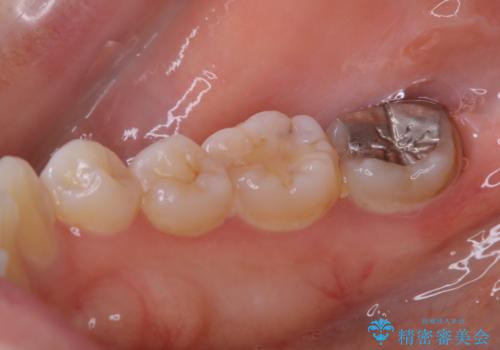

- もともとホワイトスポット(エナメル質形成不全)が全体的に目立つ歯だったので処置後ホワイトスポットがより白くなりました。

- クラウンやインレー等の補綴物には効果がありません